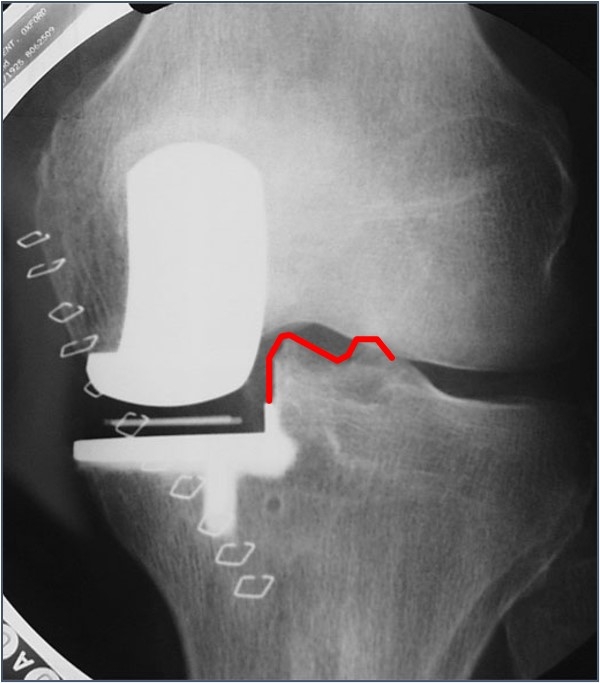

理想的垫片放置于距离外侧1mm,过远易发生垫片旋转脱位,过近易发生撞击。确保垫片不要撞击侧壁,不然—再次截骨。

防止撞击:若衬垫与骨发生撞击,衬垫可能脱位。前方研磨截骨防止前方撞击。使用骨凿截除后方骨赘以防止后方撞击。

⑤确保无撞击。